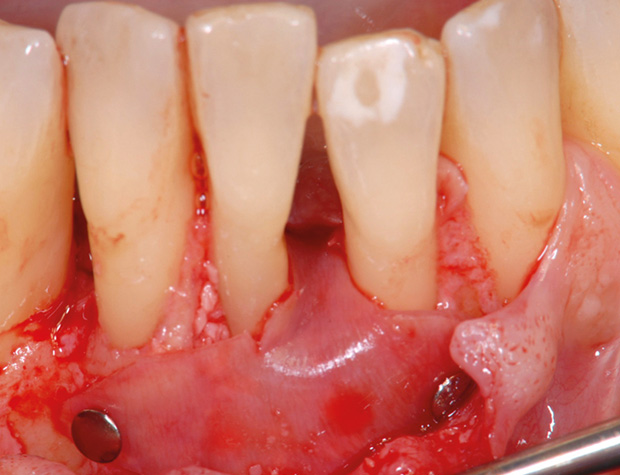

Nach der nicht-chirurgischen Parodontitis-Therapie verbleiben an stark parodontal-kompromittierten Zähnen häufig noch Resttaschen, die im Rahmen einer erfolgreichen Parodontitis-Therapie weiter behandelt werden müssen. Zu diesem Zeitpunkt stellt sich also die Frage, ob der einzelne Zahn mittels parodontalchirurgischer Verfahren erhaltungsfähig ist oder doch besser extrahiert werden sollte. Regenerative parodontalchirurgische Verfahren spielen an dieser Stelle eine große Rolle. Doch wann sollte welche chirurgische Technik, wann sollten welche regenerativen Materialien verwendet werden? Der Workshop vermittelt Kenntnisse, wann ein Zahnerhalt mittels Regeneration parodontaler Defekte erfolgreich möglich ist und wann welche chirurgischen Techniken und regenerativen Materialen zielführend sind.

HANDS-ON

Die Teilnehmer trainieren am Tiermodell verschiedene mikrochirurgische Techniken der Parodontalchirurgie. Zusätzlich werden die Schritte regenerativer Maßnahmen an unterschiedlichen Defekten (z.B. an 1-, 2- und 3-wandigen Defekten) mit den verschiedenen regenerativen Materialien geübt.